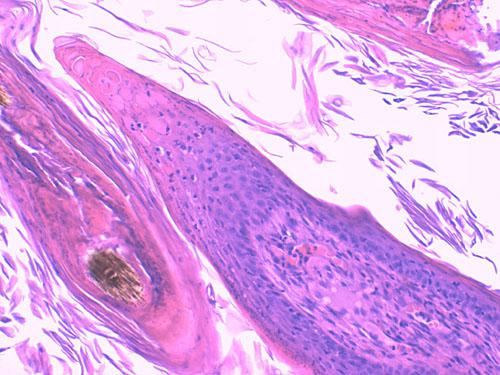

Photo 13 (Hémalun-Eosine X200) : vue rapprochée d’une papille ostiale de la Photo 12.

Elle est revêtue d’un chapeau parakératosique au sein duquel

les kératinocytes sous-cornés sont vacuolisés (vacuole cytoplasmique).

Légendes de la Photo 13 :

- Flèche truquoie : sommet d’une projection papillaire de l’épiderme hyperplasique se formant à la marge d’un ostium folliculaire

- Rond marron et ovale turquoise : infundibulum folliculaire hyperkératosiques (orthokératose)

- Rond turquoise : zone granuleuse de la papille épidermique

- Flèche jaune : kératinocytes au cytoplasme vacuolisé

- Etroiles rouges : zone de parakératose, coiffe parakératosique de la papille épidermique